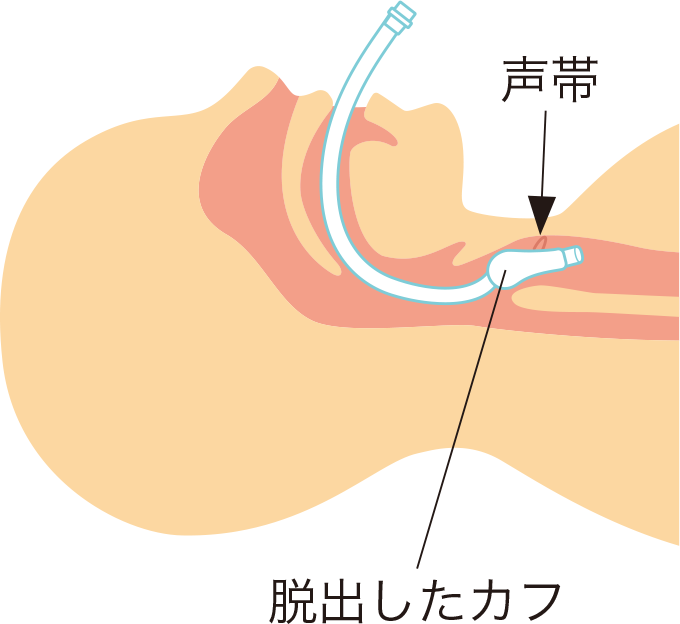

カフ圧を追加してもゴロゴロと音がしてカフリークが持続する場合は、気管チューブの移動によりカフが声門から脱出していると考えられるため、再挿管や気管チューブを適切な位置に調整する必要があります(図3)。

図3気管チューブカフの声門からの脱出